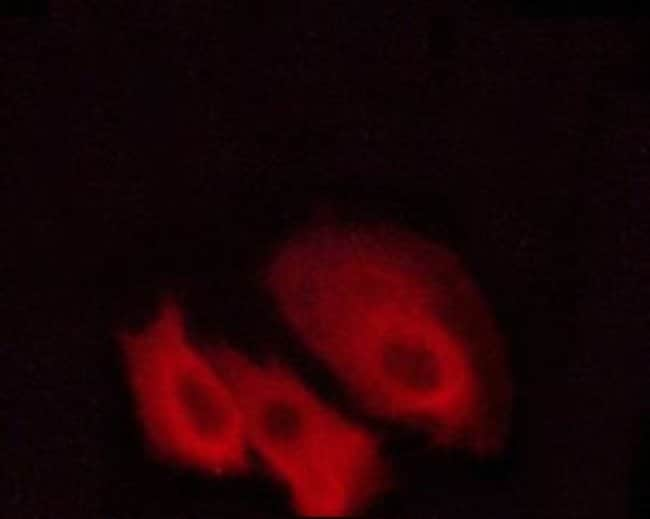

Invitrogen™ Phospho-PKC Pan (Thr497) Polyclonal Antibody

Antibody detects endogenous levels of PKC-pan only when phosphorylated at Threonine 497.

| Immunohistochemistry (Paraffin), Western Blot, Immunocytochemistry | |